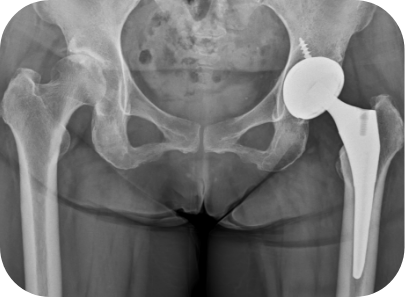

고관절 무혈성괴사 환자의 인공관절 전치환술 사례

• ▲ 수술 전

• ▲ 수술 후

고관절 퇴행성관절염 환자의 인공관절 전치환술 사례